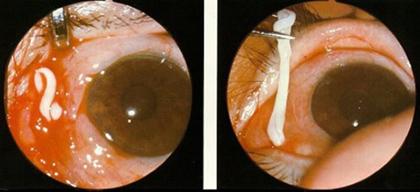

Bệnh ấu trùng sán nhái thể mắt (Ocular sparganosis)

Đây là thể bệnh điển hình nhất của nhiễm trùng sán nhái. Bệnh sán nhái ở mắt có hình ảnh đặc biệt và lâm sàng đặc trưng cho bệnh sán nhái. Các triệu chứng sớm gồm có đau mắt, chảy nước mắt sống (epiphora) và/ hoặc sa mi mắt (ptosis). Các triệu chứng khác gồm phù quanh ổ mắt và /hoặc sưng phù tương tự dấu Romana trong bệnh loétgiác mạc lộ ra. Các triệu chứng hay gặp nhất là một khối tổn thương trong mắt, nếu không điều trị thì bệnh sán nhái ở mắt có thể dẫn đến mù.

Khi ấu trùng sán vào trong mắt tạo ra một phản ứng căng nhức, nhất là phù quanh nhãn cầu, có thể đến mù nếu không can thiệp kịp thời vì ký sinh trùng di chuyển vào đến kết mạc và vào trong ổ mắt. Trong các mô ở ổ mắt, ấu trùng nằm lại phía cực sau gây phản ứng viêm, dẫn đến lồi mắt và thị lực bị ảnh hưởng, một số ca có loét giác mạc. Nói chung thể này thường gây đau mắt, nhức, kích thích, loét giác mạc chảy nước mắt, sưng phù đáng kể mi mắt.

Hình 2-3-4. Tổn thương dạng u sán nhái và sán nhái gây viêm dính kết mạc

Biểu hiện thể mắt thường là sau 1 tuần với biểu hiện mắt bị sưng, đỏ, giảm thị lực và đôi khi chảy nước mẳt ắt dễ nhầm lẫn với các bệnh về mắt khác, nhất là các rối loạn tổn thương giác mạc, khiến thầy thuốc nếu không nghĩ đến dễ chẩn đoán muộn và điều trị không kịp thời, ngay cả người bệnh tự ý dùng thuốc điều trị cho chính mình bằng một số thuốc dung dịch nhỏ mắt. Đến khi đi khám và xét nghiệm chuyên khoa mới phát hiện ra bệnh là do loài ấu trùng sán nhái S. erinacei. Bệnh có thể gây tổn thương và nhiễm trùng lan rộng đến nhãn cầu và hốc mắt và nếu có thể bội nhiễm đi kèm thì bệnh thêm trầm trọng.

Hình 5-6-7. Thương tổn các bộ phận do sán nhái gây ra tại mắt